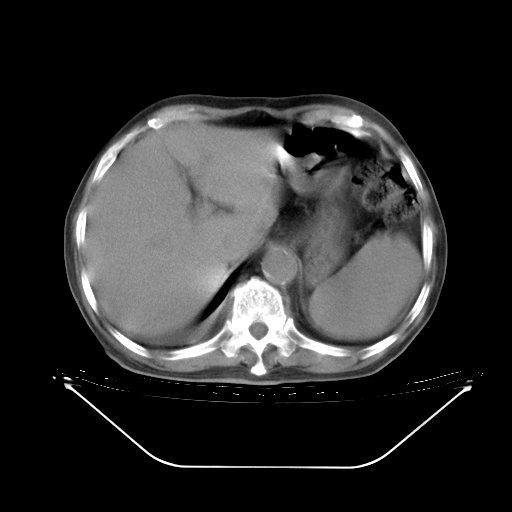

今天复查肺部CT,发现双肺广泛磨玻璃样改变。所以我把3月19日和5月9日相隔50天的肺部CT上传。请大家会诊。

5月9日肺部CT(在4月27日齐鲁医院肺部CT描述部分肺组织磨玻璃样改变,12天后肺组织广泛磨玻璃样改变)

2009年5月9日肺部CT

大致读了系列胸部CT:纵隔窗无明显异常,肺窗:从4、27至今:主要是双肺中下野外带可见毛玻璃样改变,目前处于急性肺泡炎阶段,至于原因考虑1、结替组织或胶原血管性疾病所致?2、恶性疾病如恶组在肺部所致的表现或细支气管肺泡癌?3、药物或其它原因如肺蛋白沉着症所致肺泡炎目前不太可能?总之,明天就去请我院的呼吸科、感染科、血液科和临免专家会诊哈。